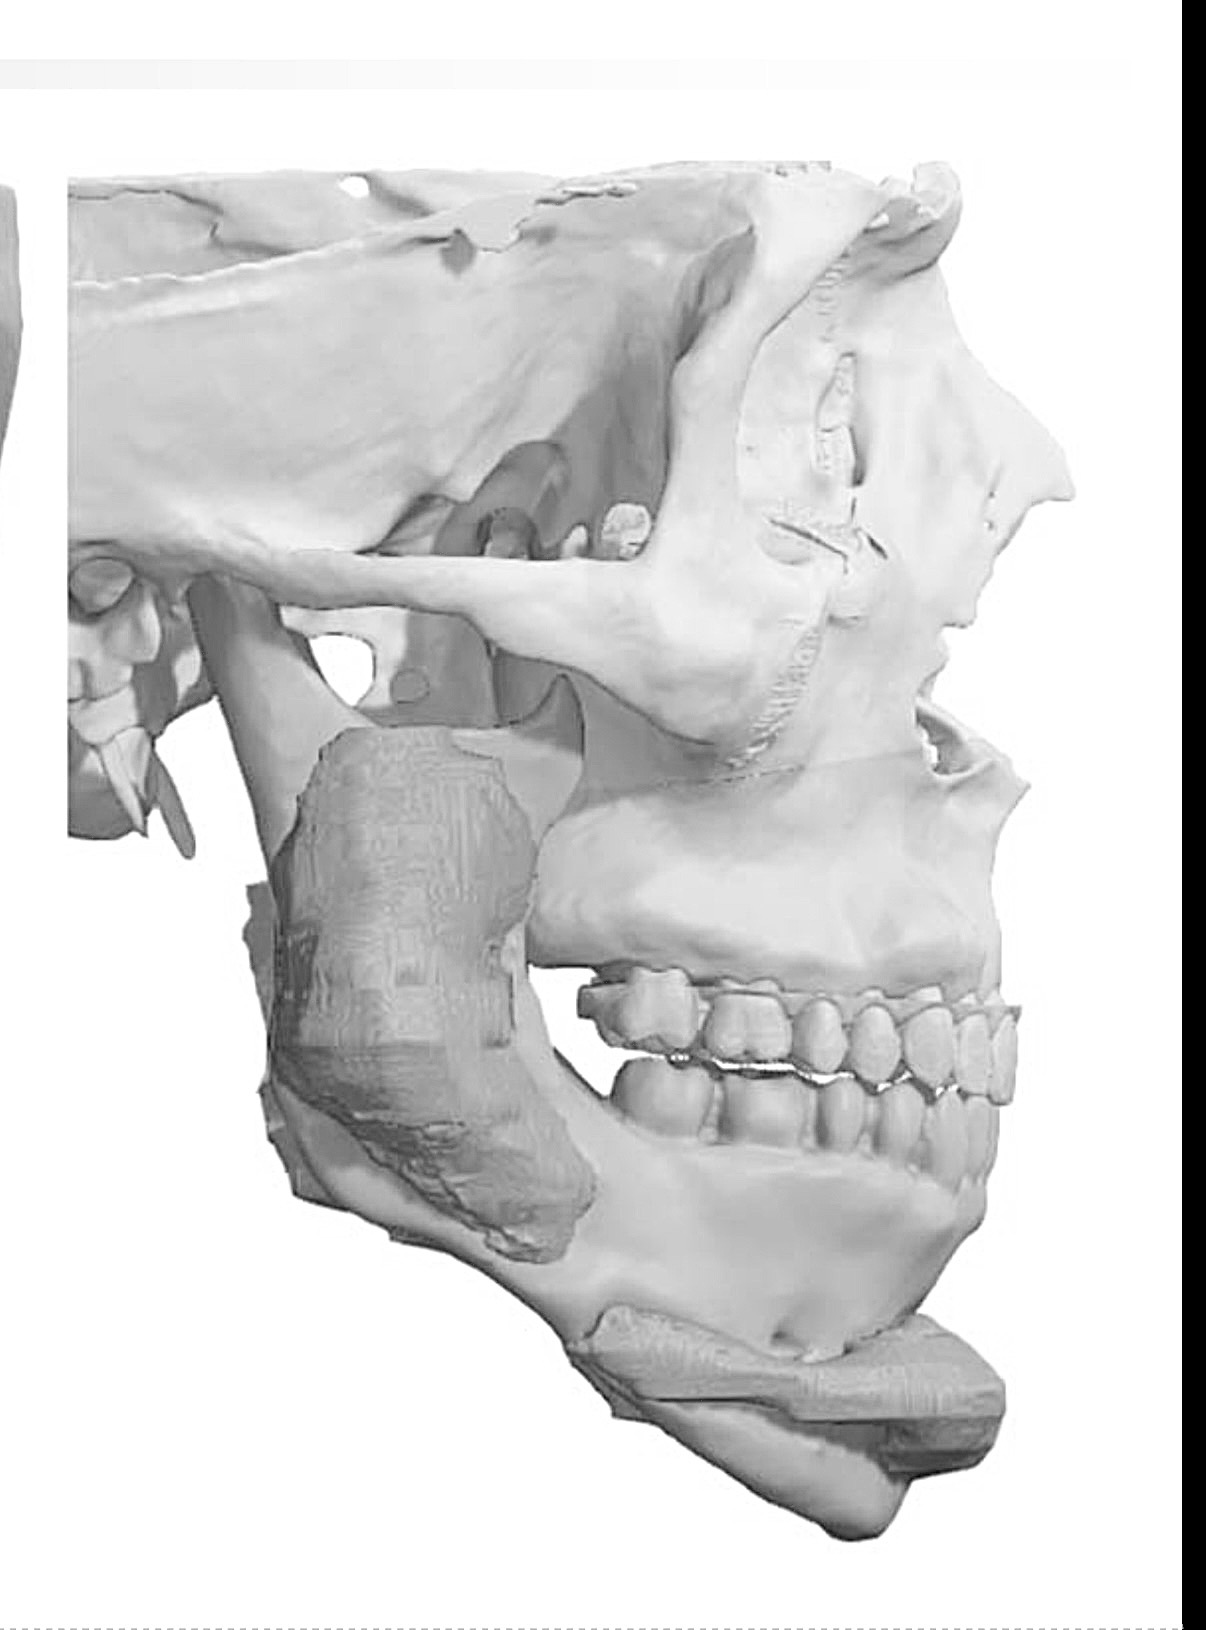

Getting a Le fort 1 with sliding genio to shorten my long face, replacing my jaw implants and adding cheek implants. Doing 6mm impaction with 4mm advancement. No BSSO. What do you guys think of the implant design? Angle too low? Attached pics are before and after